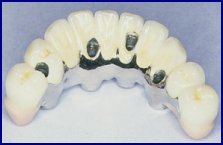

Diferença entre restauração a amálgama e a compósito

Se as cáries são descobertas nas suas fases iniciais, o tratamento é muito simples, consistindo apenas de retirar o esmalte cariado, e preencher com um material igual ao dente. Quando só são diagnosticadas já em fases avançadas, quando já dói ou já partiu o dente os tratamentos são mais difíceis podendo obrigar a várias sessões, para limpar o interior do dente, e tirar todo o tecido necrosado e infectado dos canais. Daí o interesse em tentar tratar as cáries logo que delas haja suspeita, já que torna os tratamentos muito mais simples, mais rápidos e seguramente menos dispendiosos.